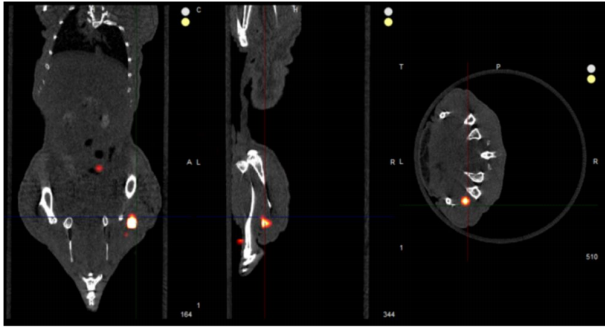

骨靶向-生物分布

对骨靶向结合荧光探针进行全身骨结构三维荧光断层扫描

检测在不同骨组织中的生物分布。